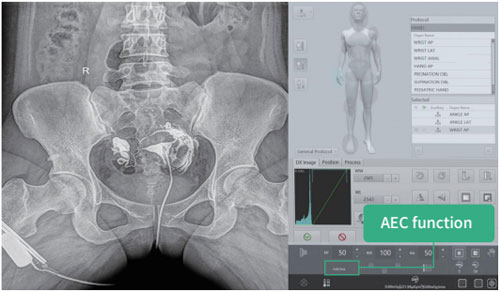

● Intelligent control exposure time, more efficient.

● Intelligent control of light sensitivity according to different parts.

● Reduces operational difficulties and shortens the workflow.

● Intelligent image acquisition and processing workstation, integrating registration, photography control, image processing and transmission, report printing, film, printing and other functions, with a high degree of integration.

● Humanized menu design makes the operation more convenient. It can switch perspective and shooting modes with one button to optimize the workflow.

● Excellent image post-processing technology.Effectively reduce the dose, improve image quality.

● Image enhancement

● Advanced circle image processing tools

● Window width and level adjustment

● Customized interface flow

● Image cropping function

● Large size monitor